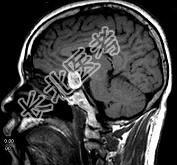

- 单项选择题男性,55岁, 头痛一年余,两个小时前突然出现剧烈头痛, MRI检查如图所示,最可能的诊断为 ( )

E、动脉瘤